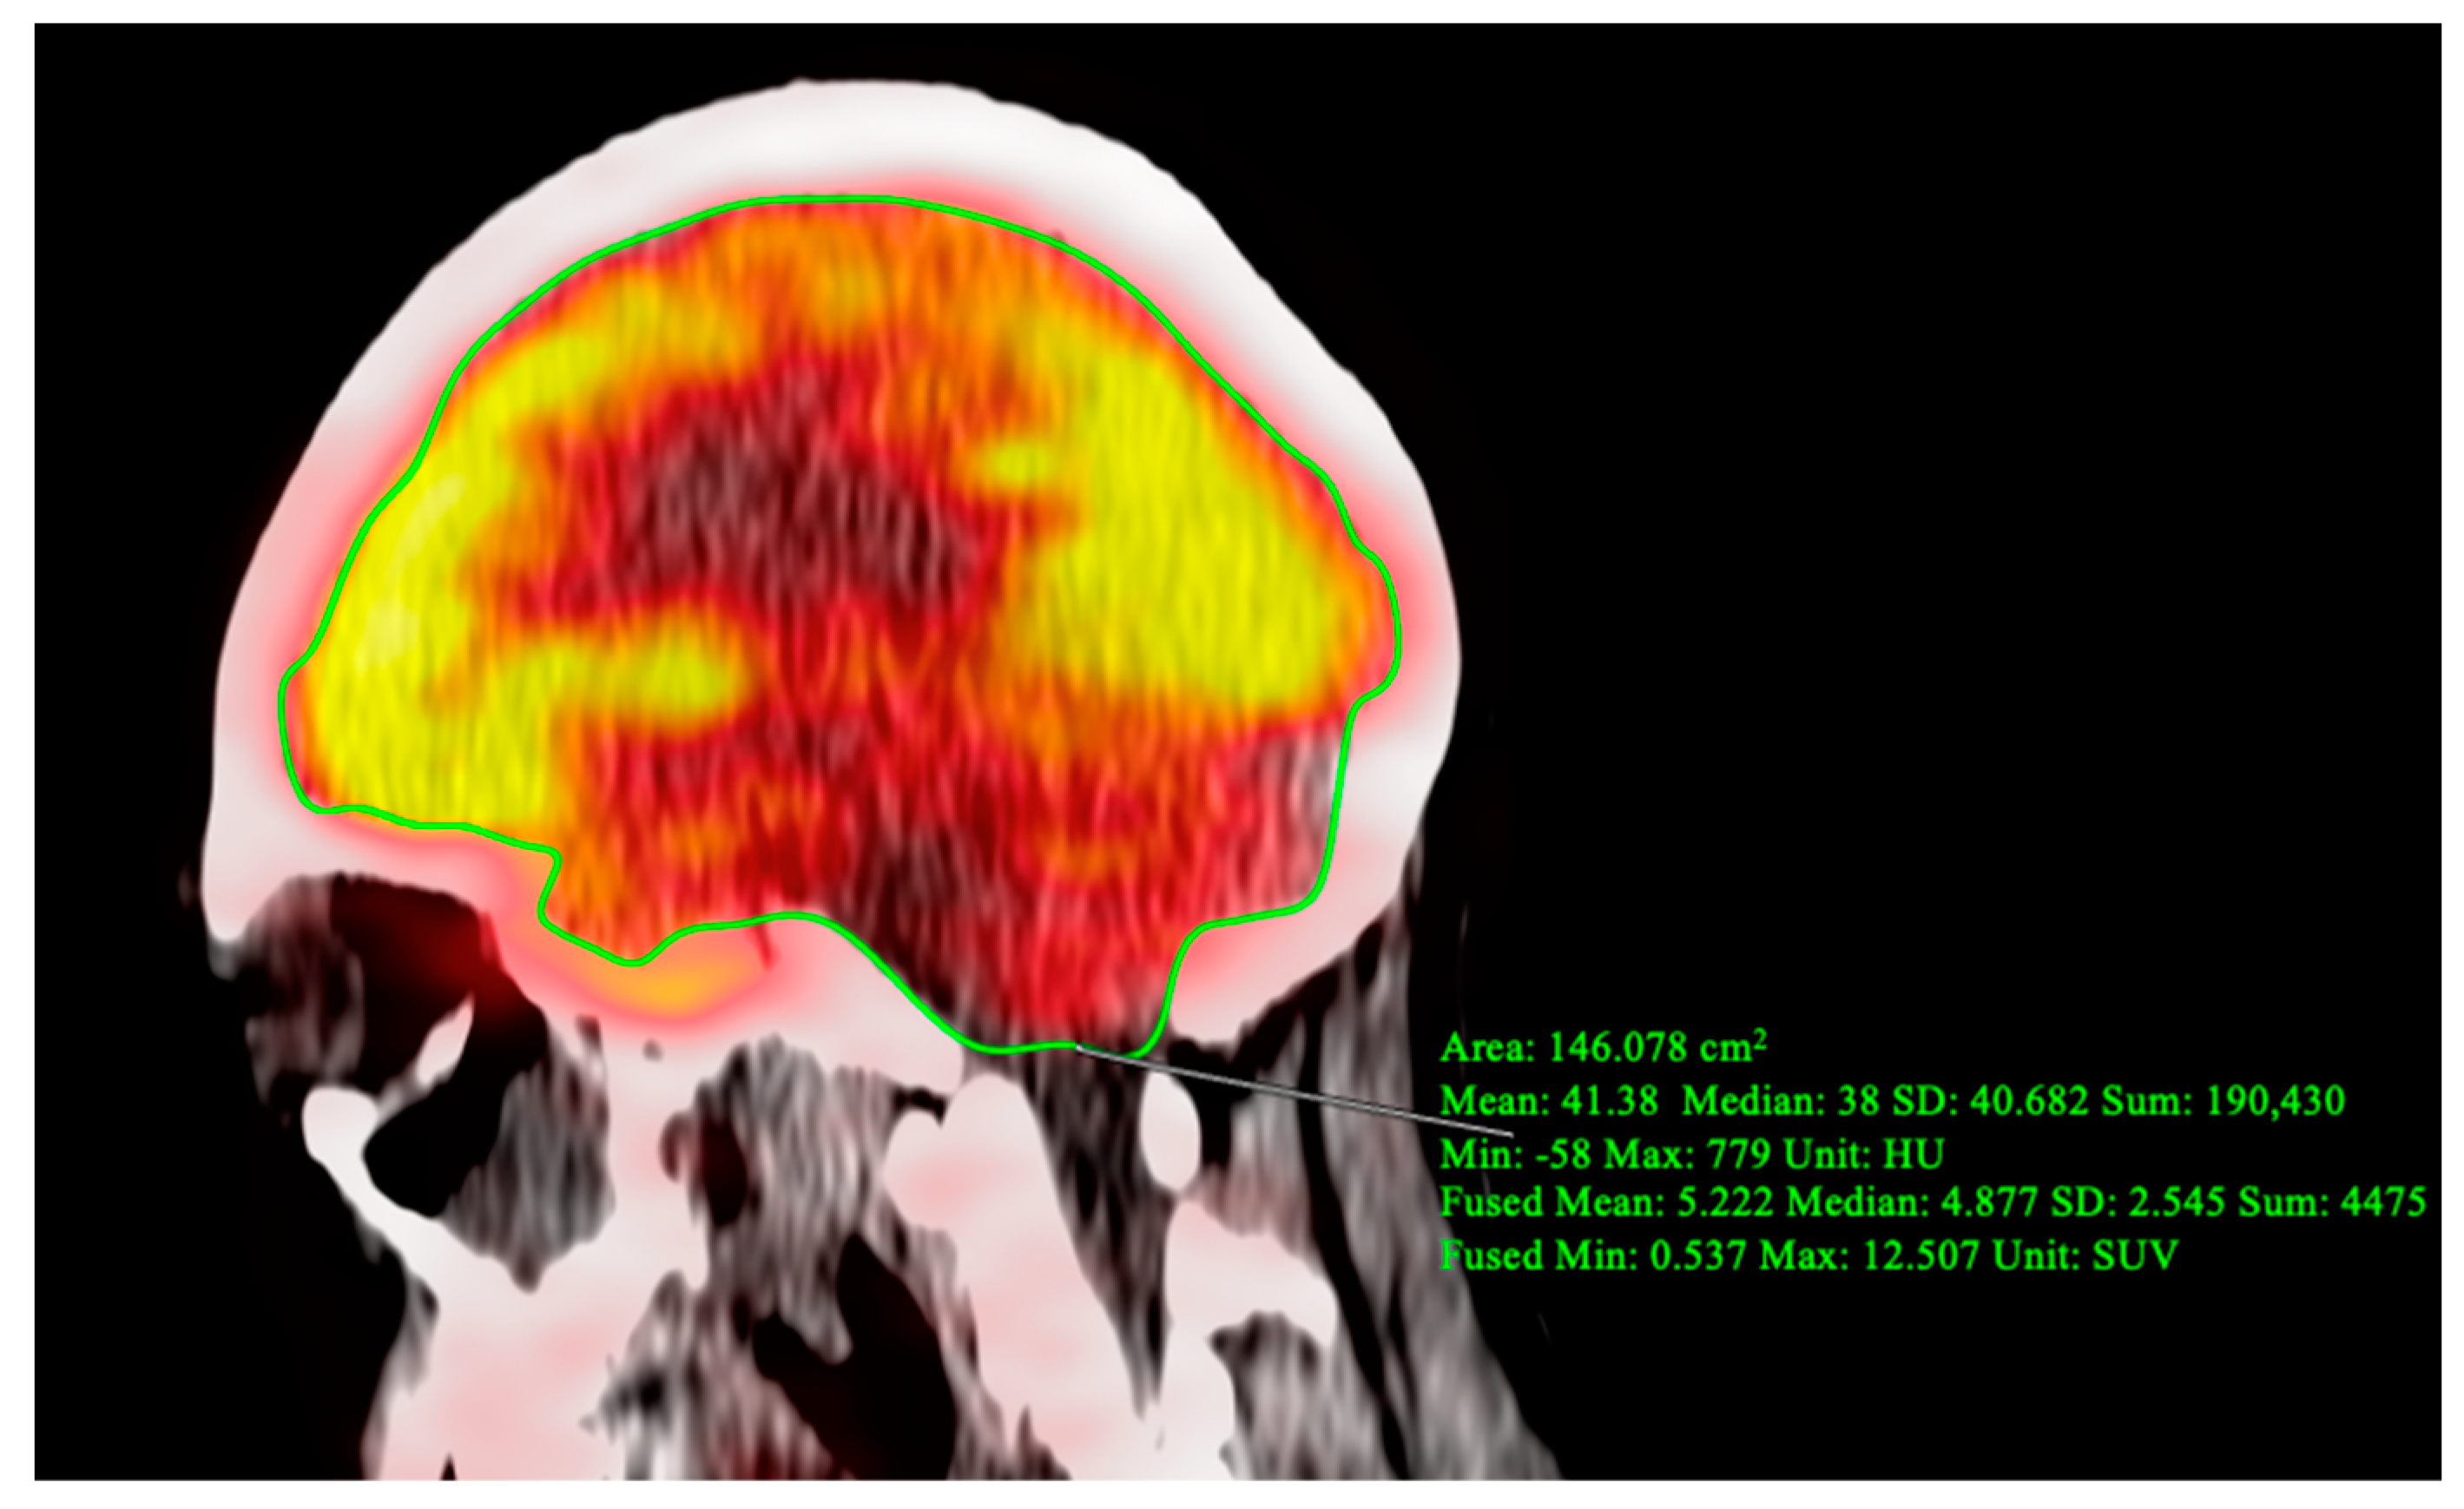

2. Case Report